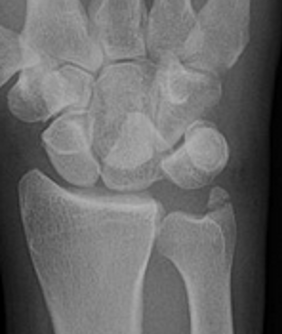

AP X-ray

Disruption of Gilula's 3 smooth carpal arcs / triangular lunate

Normal versus disruputed Gilula's carpal arcs

Piece of pie / triangular appearance of lunate